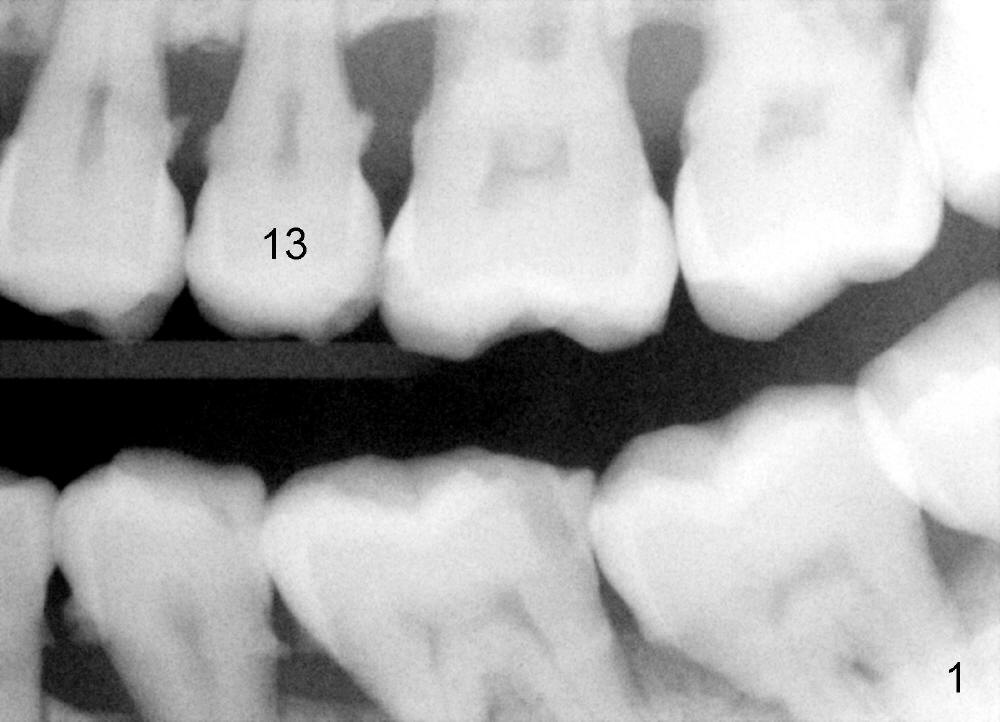

A 57-year-old man has history of chronic periodontitis (Fig.1,2, taken 9 and 7 years ago, respectively). Last April the tooth #13 had crown fracture (Fig.3). He returned to clinic for scaling & root planing last week (Fig.4). Fig.3,4 show long root and bone. Arrowheads in Fig.4 indicate the sinus floor.

If the buccolingual (B-L) width of the extracted root is much wider than the mesiodistal (M-D) one, a D1 (4 (B-L) x 3.5 (M-D) cervical) or D2 (5.5x3.5) implant will be selected (20 mm long). To reduce tapping and vibration, 1.5 mm pilot drill and 2.5 mm reamer will be used to start osteotomy at 20 mm deep, 3 mm reamer at 17 mm if needed, followed by D osteotomes. Save autogenous bone for grafting buccally later.

The root of the extracted tooth is not so similar to the D implant. So a tapered implant is placed.